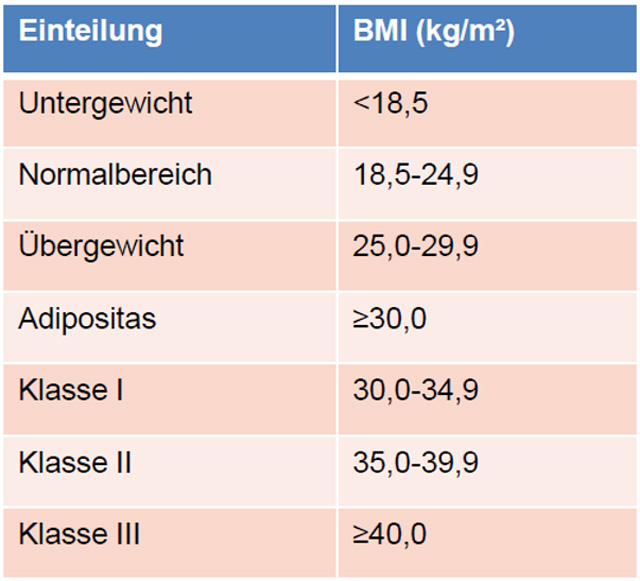

Der Body Mass Index

Zusammen mit der Körpergrösse kann über die Formel Körpergewicht (Kg) /Körpergrösse2 (m2) der so genannte Body Mass Index, der BMI berechnet werden.

Auch dieser Wert unterliegt gewissen Limitationen.

Zwar definiert die WHO über den BMI Übergewicht und Adipositas (Fettleibigkeit), jedoch ist der Wert gerade bei Sportlern schwierig zu bewerten, da der oftmals erhöhte Anteil der Muskelmasse den Wert verfälschen kann.

Body Mass Index Tabelle